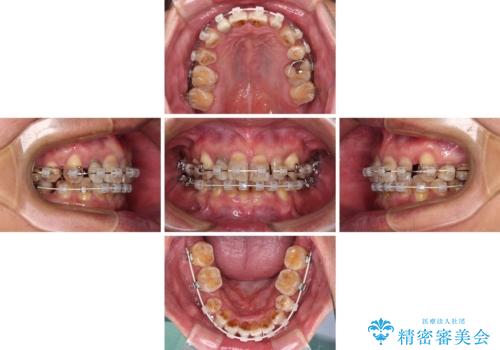

- 骨格的な咬み合わせのズレ、前歯のデコボコとクロスバイトを気にして来院された患者様です。

全額的にデコボコが強いため、上下左右の小臼歯計4歯を抜歯し、ワイヤー装置による矯正治療を行うこととしました。

抜歯する歯の一部をセオリーである第一小臼歯ではなく、第二小臼歯にすることで、骨格的なずれをカバーするように計画しました。